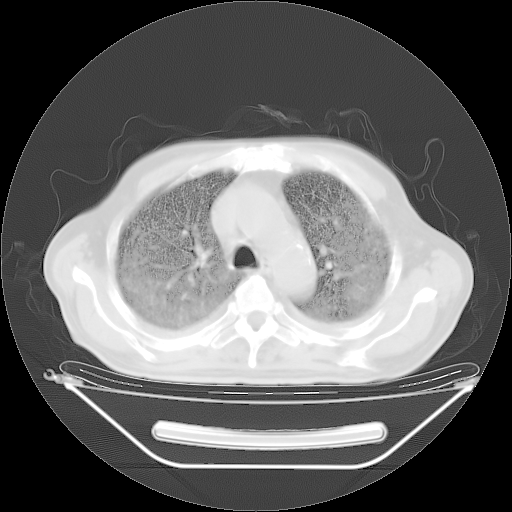

今天复查肺部CT,发现双肺广泛磨玻璃样改变。所以我把3月19日和5月9日相隔50天的肺部CT上传。请大家会诊。

2009年3月19日肺部CT片。

2009年3月19日肺部CT

大致读了系列胸部CT:纵隔窗无明显异常,肺窗:从4、27至今:主要是双肺中下野外带可见毛玻璃样改变,目前处于急性肺泡炎阶段,至于原因考虑1、结替组织或胶原血管性疾病所致?2、恶性疾病如恶组在肺部所致的表现或细支气管肺泡癌?3、药物或其它原因如肺蛋白沉着症所致肺泡炎目前不太可能?总之,明天就去请我院的呼吸科、感染科、血液科和临免专家会诊哈。